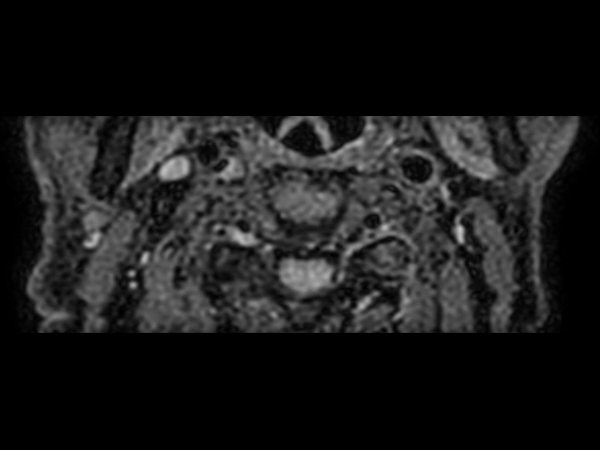

Patient with a neck stenosis. Compressed SENSE is used to shorten the total exam time.

3D T2w TSE Black Blood - Compressed SENSE